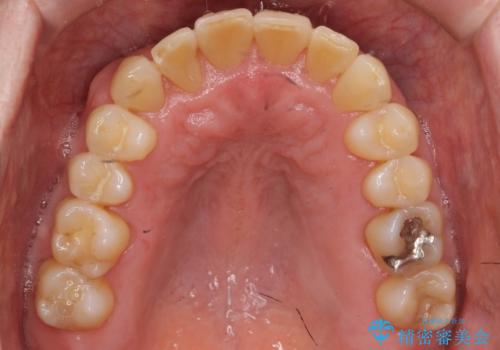

矯正治療後、右下のインレーブリッジおよび左下の銀歯のやりかえを行なっています。

右上の八重歯は、右上の奥歯を矯正用ミニスクリューを用いて遠心移動を行い解消しました。

下の前歯はIPR(エナメル質を薄く削り歯を小さくする処置)を行なっています。